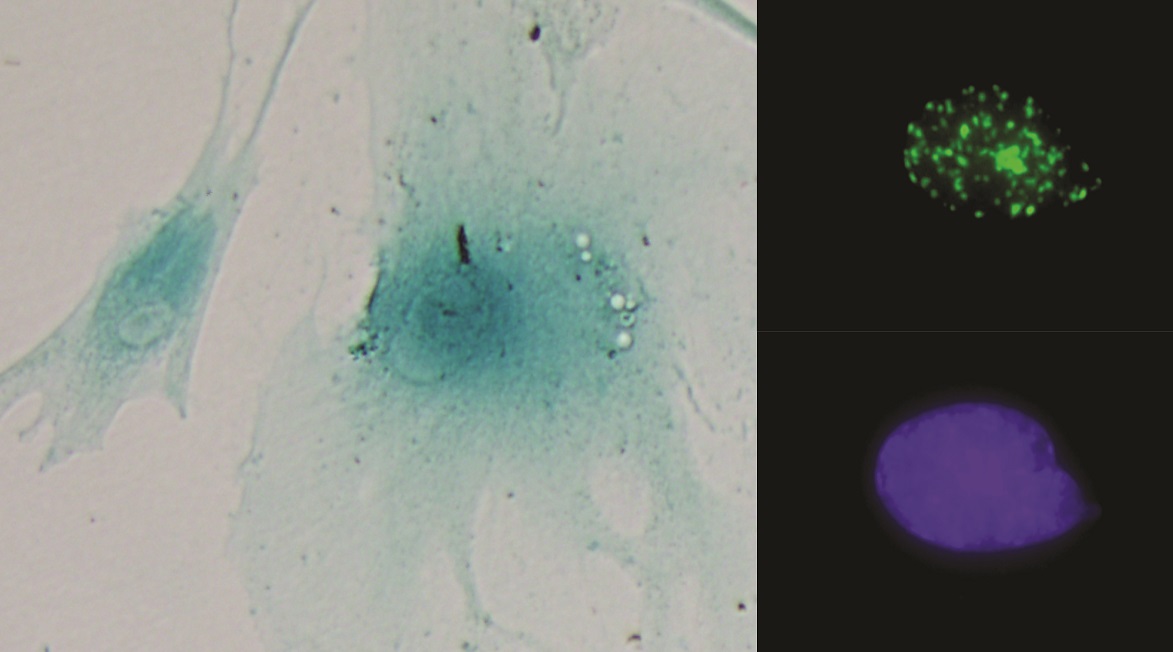

Desarrollan un modelo para el trasplante de islotes humanos a ratones inmunodeficientes con diabetes inducida por streptozocina